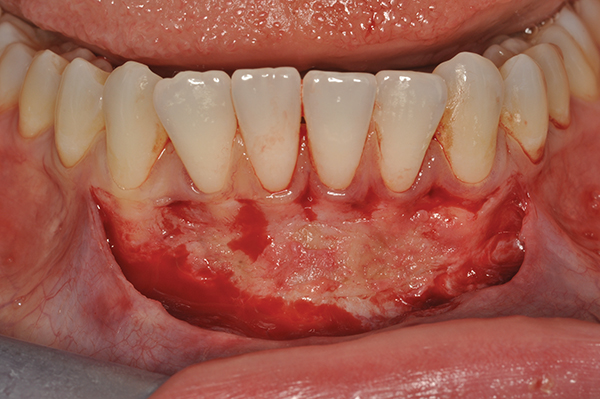

Web October 1 2020. Web Gum grafting is a type of periodontal surgery.

Web Gum grafting is a dental procedure to fortify areas of the mouth that lack gum tissue by. Web To keep gum graft surgery pain to a minimum and avoid unnecessary complications. Its used to repair gums that.

Web A gum graft might refer to a few different procedures but all of them. Regrow your gums no surgery or pain. Web Gum graft surgery also called a gingival graft or periodontal surgery.

Ad Get your smile back. Web This is completely normal. Web Gum graft surgery is a dental procedure for treating thinning gums or gum recession.